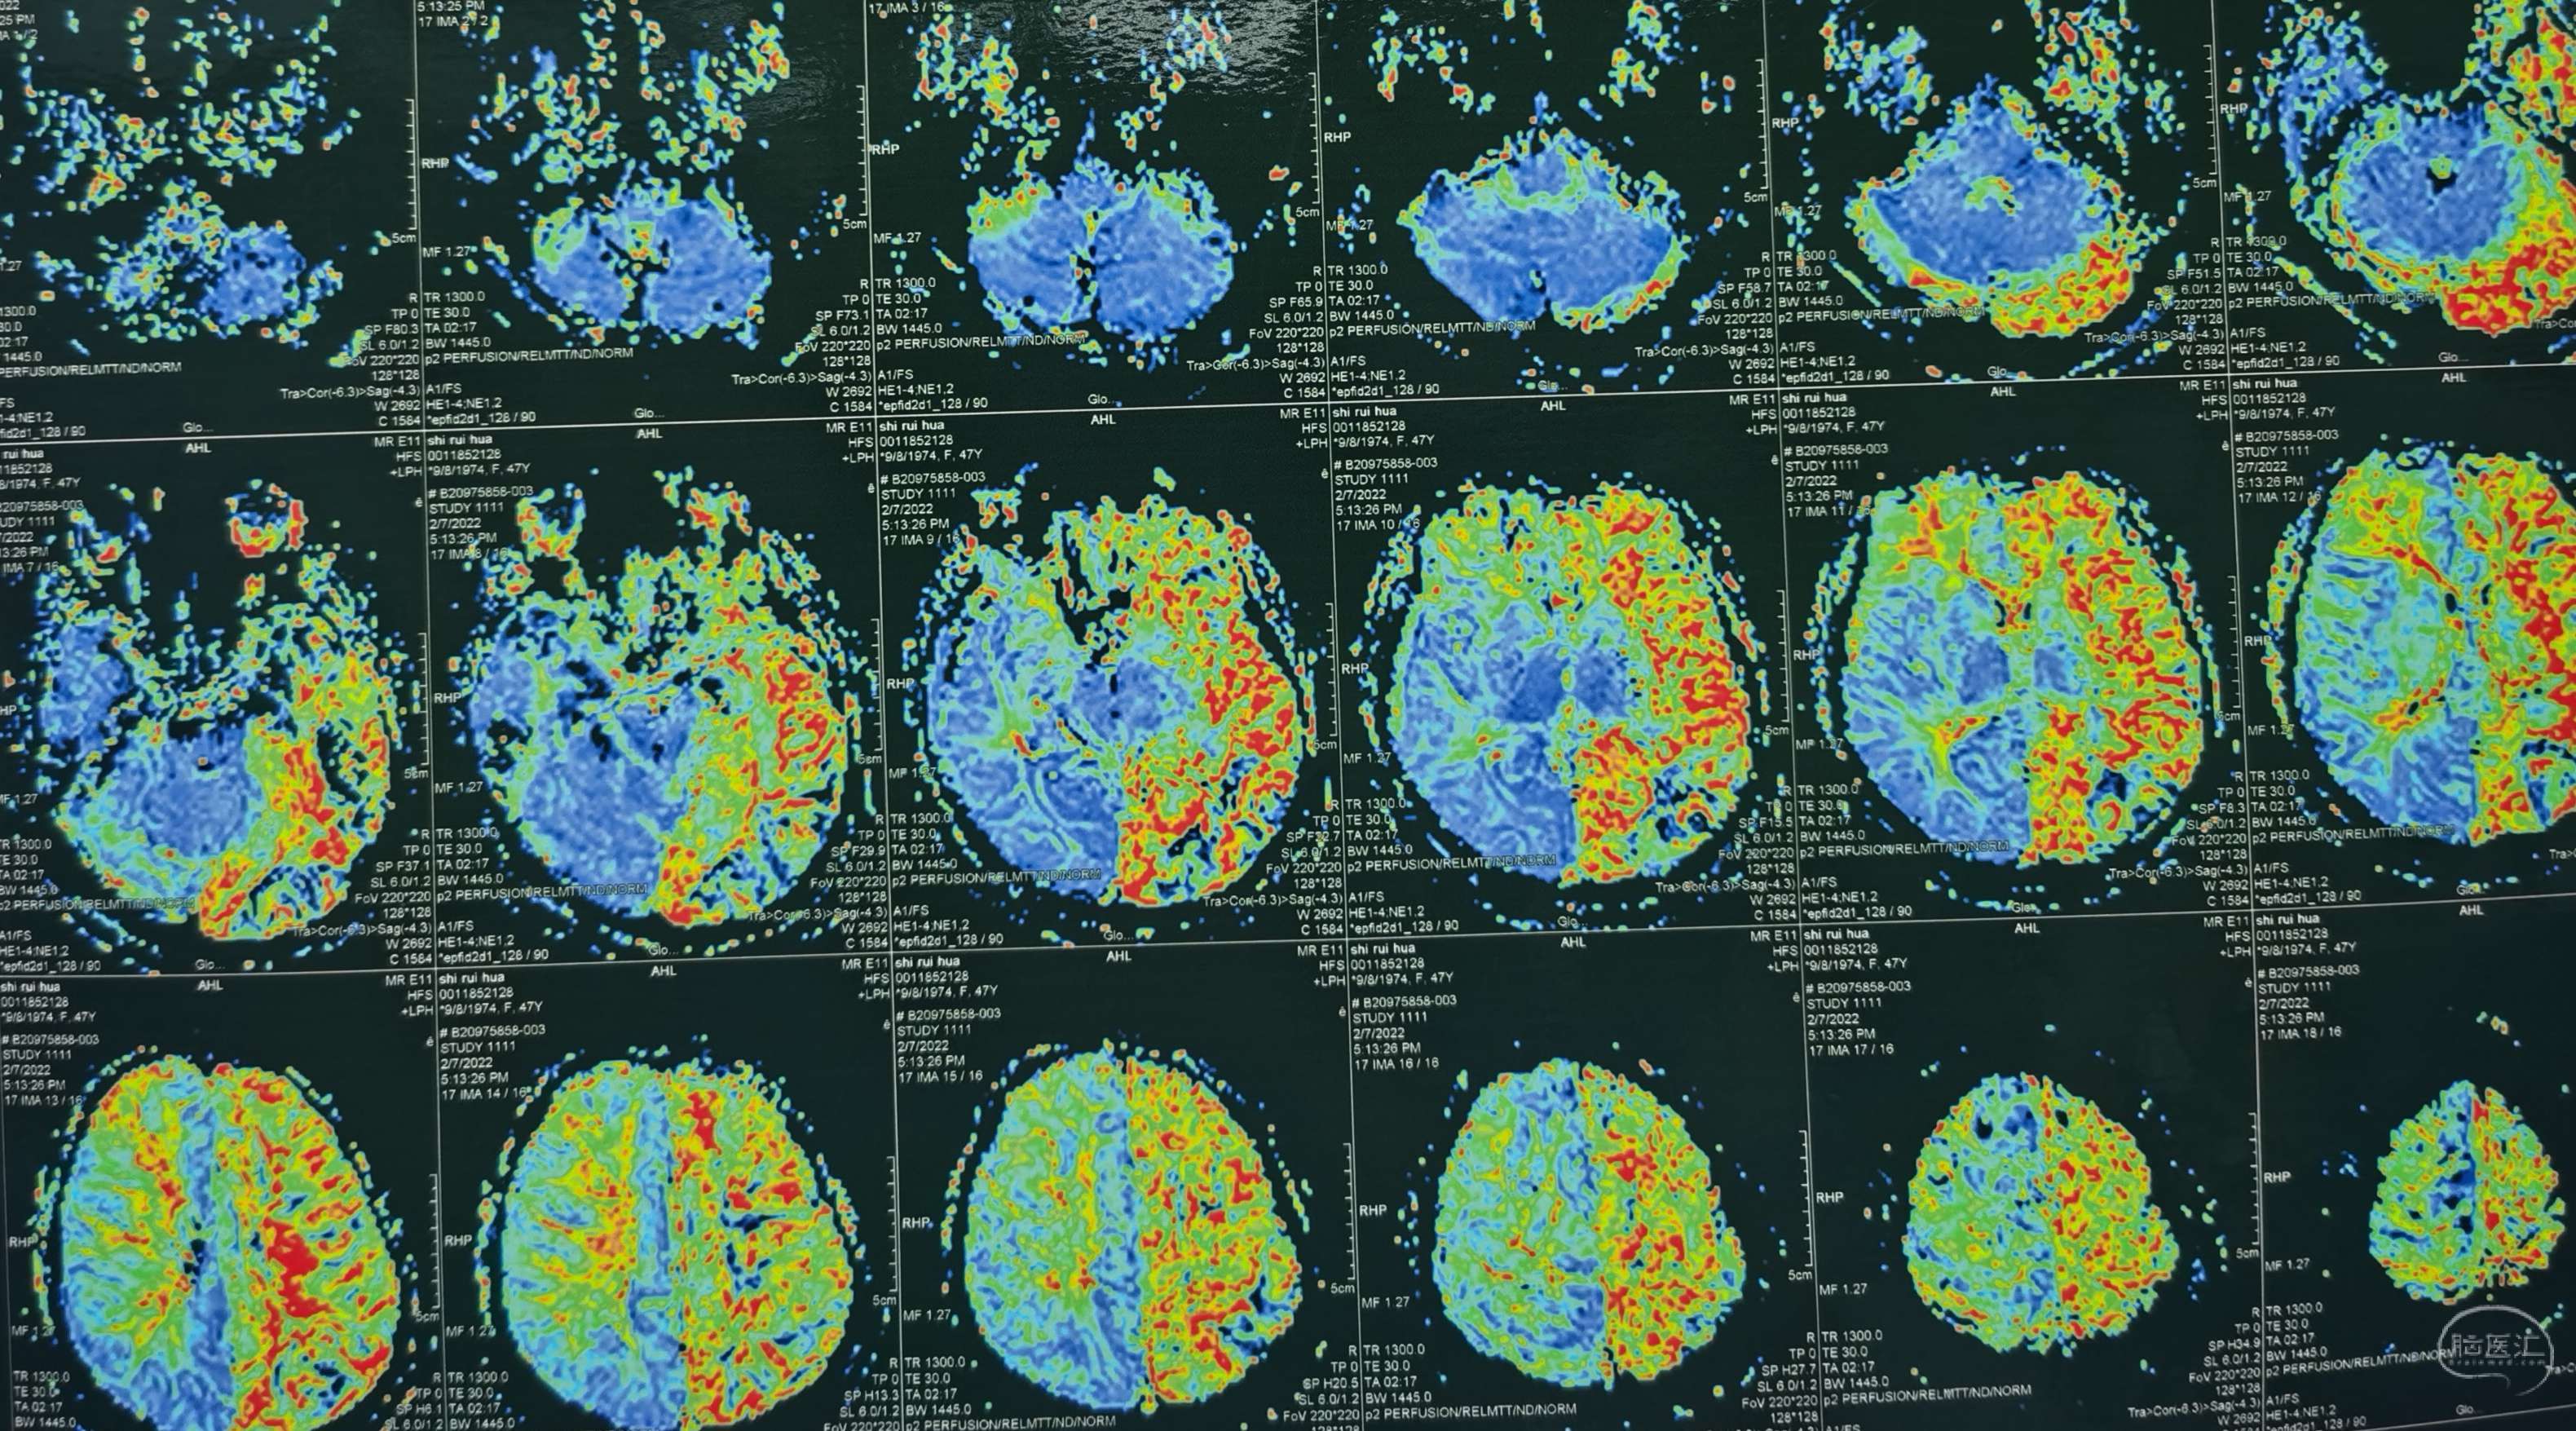

脑灌注提示:左侧大脑半球低灌注缺血。

脑灌注提示:右侧大脑半球低灌注缺血。

脑灌注提示:双侧大脑半球低灌注缺血。

脑灌注提示:双侧大脑半球低灌注缺血。

脑灌注提示:双侧大脑半球低灌注缺血。